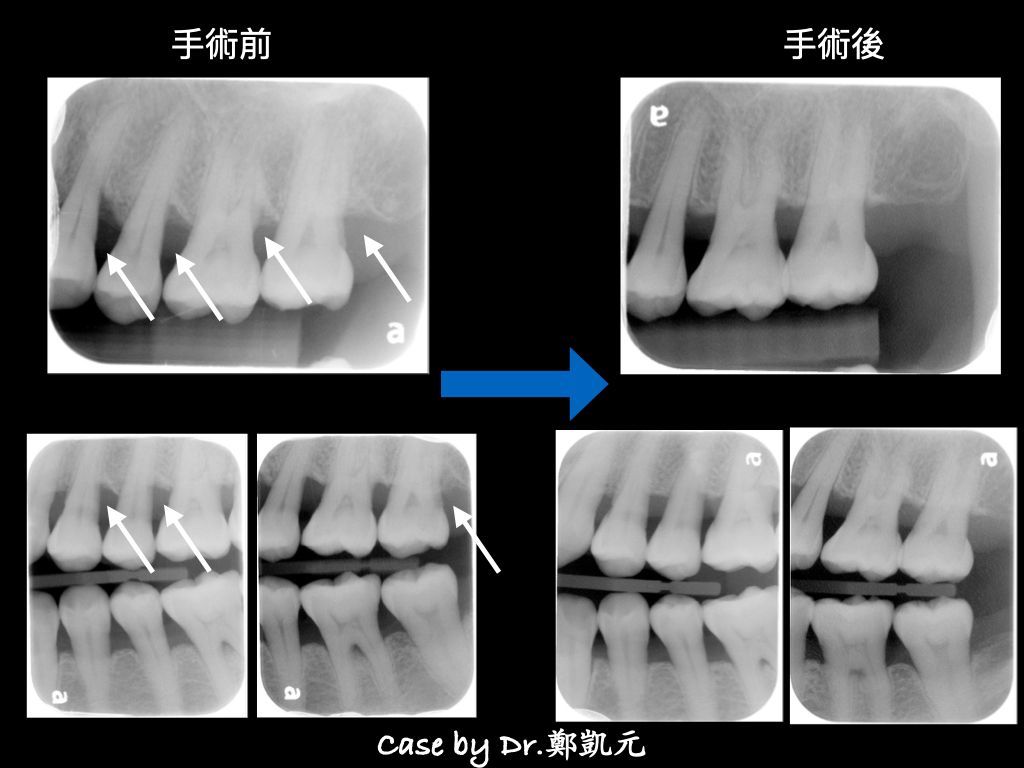

只要把造成牙周病的致病菌、結石、發炎組織徹底清除,牙周就能恢復健康。滅菌越徹底,自體修復的效果越好,能減少不必要的牙周翻瓣手術

修整不規則的骨頭破壞,以利牙周組織癒合,恢復牙周健康